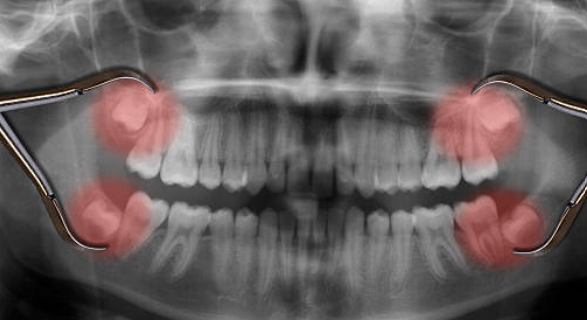

안녕하세요. 사랑니를 발치한 후에는 상처가 잘 아물도록 적절한 식습관을 유지하는 것이 매우 중요합니다. 무리한 식사는 출혈, 감염, 통증 등을 유발할 수 있으므로 주의해야 합니다. 지금부터 사랑니 발치 후 안전하게 식사하는 방법과 피해야 할 음식에 대해 자세히 알아보겠습니다.

사랑니 발치 후에는 상처 부위가 매우 민감하며 잘못된 식습관이 회복 속도를 늦출 수 있습니다. 올바른 식사 습관을 유지하면 통증을 줄이고 감염 위험을 낮추며 빠른 회복을 돕습니다.